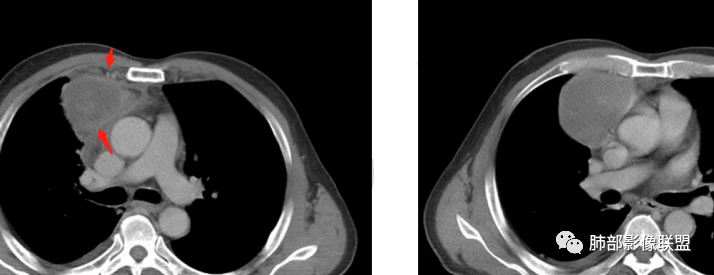

廖鹏飞:可疑胸腺动脉进入肿块

廖鹏飞:考虑胸腺瘤合并感染,畸胎瘤待排

周围脂肪间隙密度增高,内部小点状很低密度影

右侧少量胸水

19日,4天后, 内部低密度影有,周围渗出增多,胸水增多

薄膜状强化

影像上周围病灶变化明显

脂肪密度明显,还有钙化、囊性病变,支持含脂质类病变破裂

周围是化学性炎症或出血所致

肿瘤样病变破裂所致纵隔炎应该没错

南边:肿瘤或肿瘤样病变破裂所致纵隔炎,这是大方向

结果:符合B型胸腺瘤伴出血,坏死囊性变,局部脓肿形成